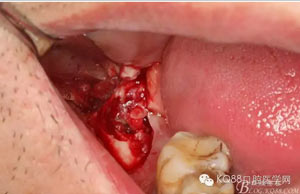

圖6.行角形瓣切開、翻瓣、暴露骨面,可見48牙冠表面有炎性肉芽組織

圖7.高速牙鉆去骨。逐漸可見48的牙冠

圖8.刮除牙冠表面的肉芽組織后,可見48 的牙冠